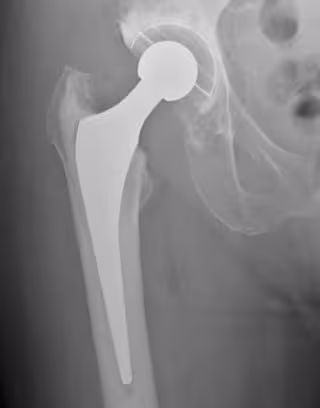

Radiografía de reemplazo de cadera

MUSCULOSKELETAL RESEARCH UNIT, UNIV. OF BRISTOL

Un reemplazo de cadera consiste principalmente en dos componentes, uno que reemplaza la bola y otro que reemplaza el zócalo. Existe una variación en la forma en que estas partes se fijan al hueso, así como en los materiales utilizados para crear la superficie de rodamiento (contacto).